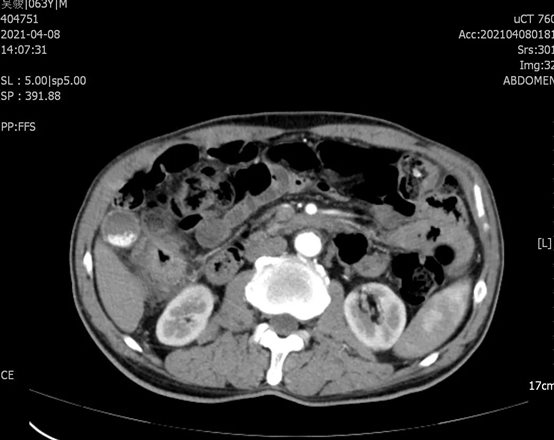

该患者因“排便习惯改变2月余,加重2天”收入我院消化内科,积极对症治疗后行结肠镜发现:距离肛缘18cm直乙结肠可见一巨大5*6cm肿块,占肠腔一圈,导致管腔狭窄,无法继续进镜。病理提示:腺癌。经会诊后转入普外科,术前检查评估,直乙结肠癌(cT3N1M0),同时发现升结肠肝曲处结肠壁增厚,恶性肿瘤可能,炎症不能除外。针对结肠肝曲恶性占位不能排除,杨孙虎主任提出了缜密的手术方案和计划。手术如期进行,术中探查结肠肝曲肿物,约5*4cm大小,质硬,冰冻,提示:腺癌。确定是多原发性大肠癌,杨孙虎主任决定一次手术完成两个肠段的根治性治疗。